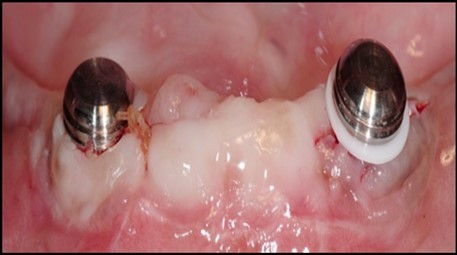

Post operatively after 3 months, osseointegration was evaluated clinically and radiographically (Figure 5a,b) and the implants were well prepared to receive the prosthesis. The second stage surgery was performed in which cover screws were removed and healing abutment were inserted into the implants (Figure 6). After a time period of two weeks, peri-implant soft tissue healing was examined, and existing denture was relined after relieving at the abutment site. Later, the healing abutment is removed using a 1.25 mm hex driver. Internal portion of the implant is irrigated and dried to make sure if it is free of debris and soft tissue. A periodontal probe was used to measure the gingival cuff height at the right and left canine site of implant location. Selected ball abutment were placed onto each implant using 1.25 mm hex driver and 30 Ncm torque wrench (Figure 7A).

Figure 5.a,b. Post-insertion radiographics in the mandibular area right,left,

Figure 7.(A) View of 2.0mm and 5.0mm post Locator Abutments with a 2.0mm post. (B) Placement of the Locator Abutment after the well of implant has been cleaned with alcohol on a cotton-tipped applicator.